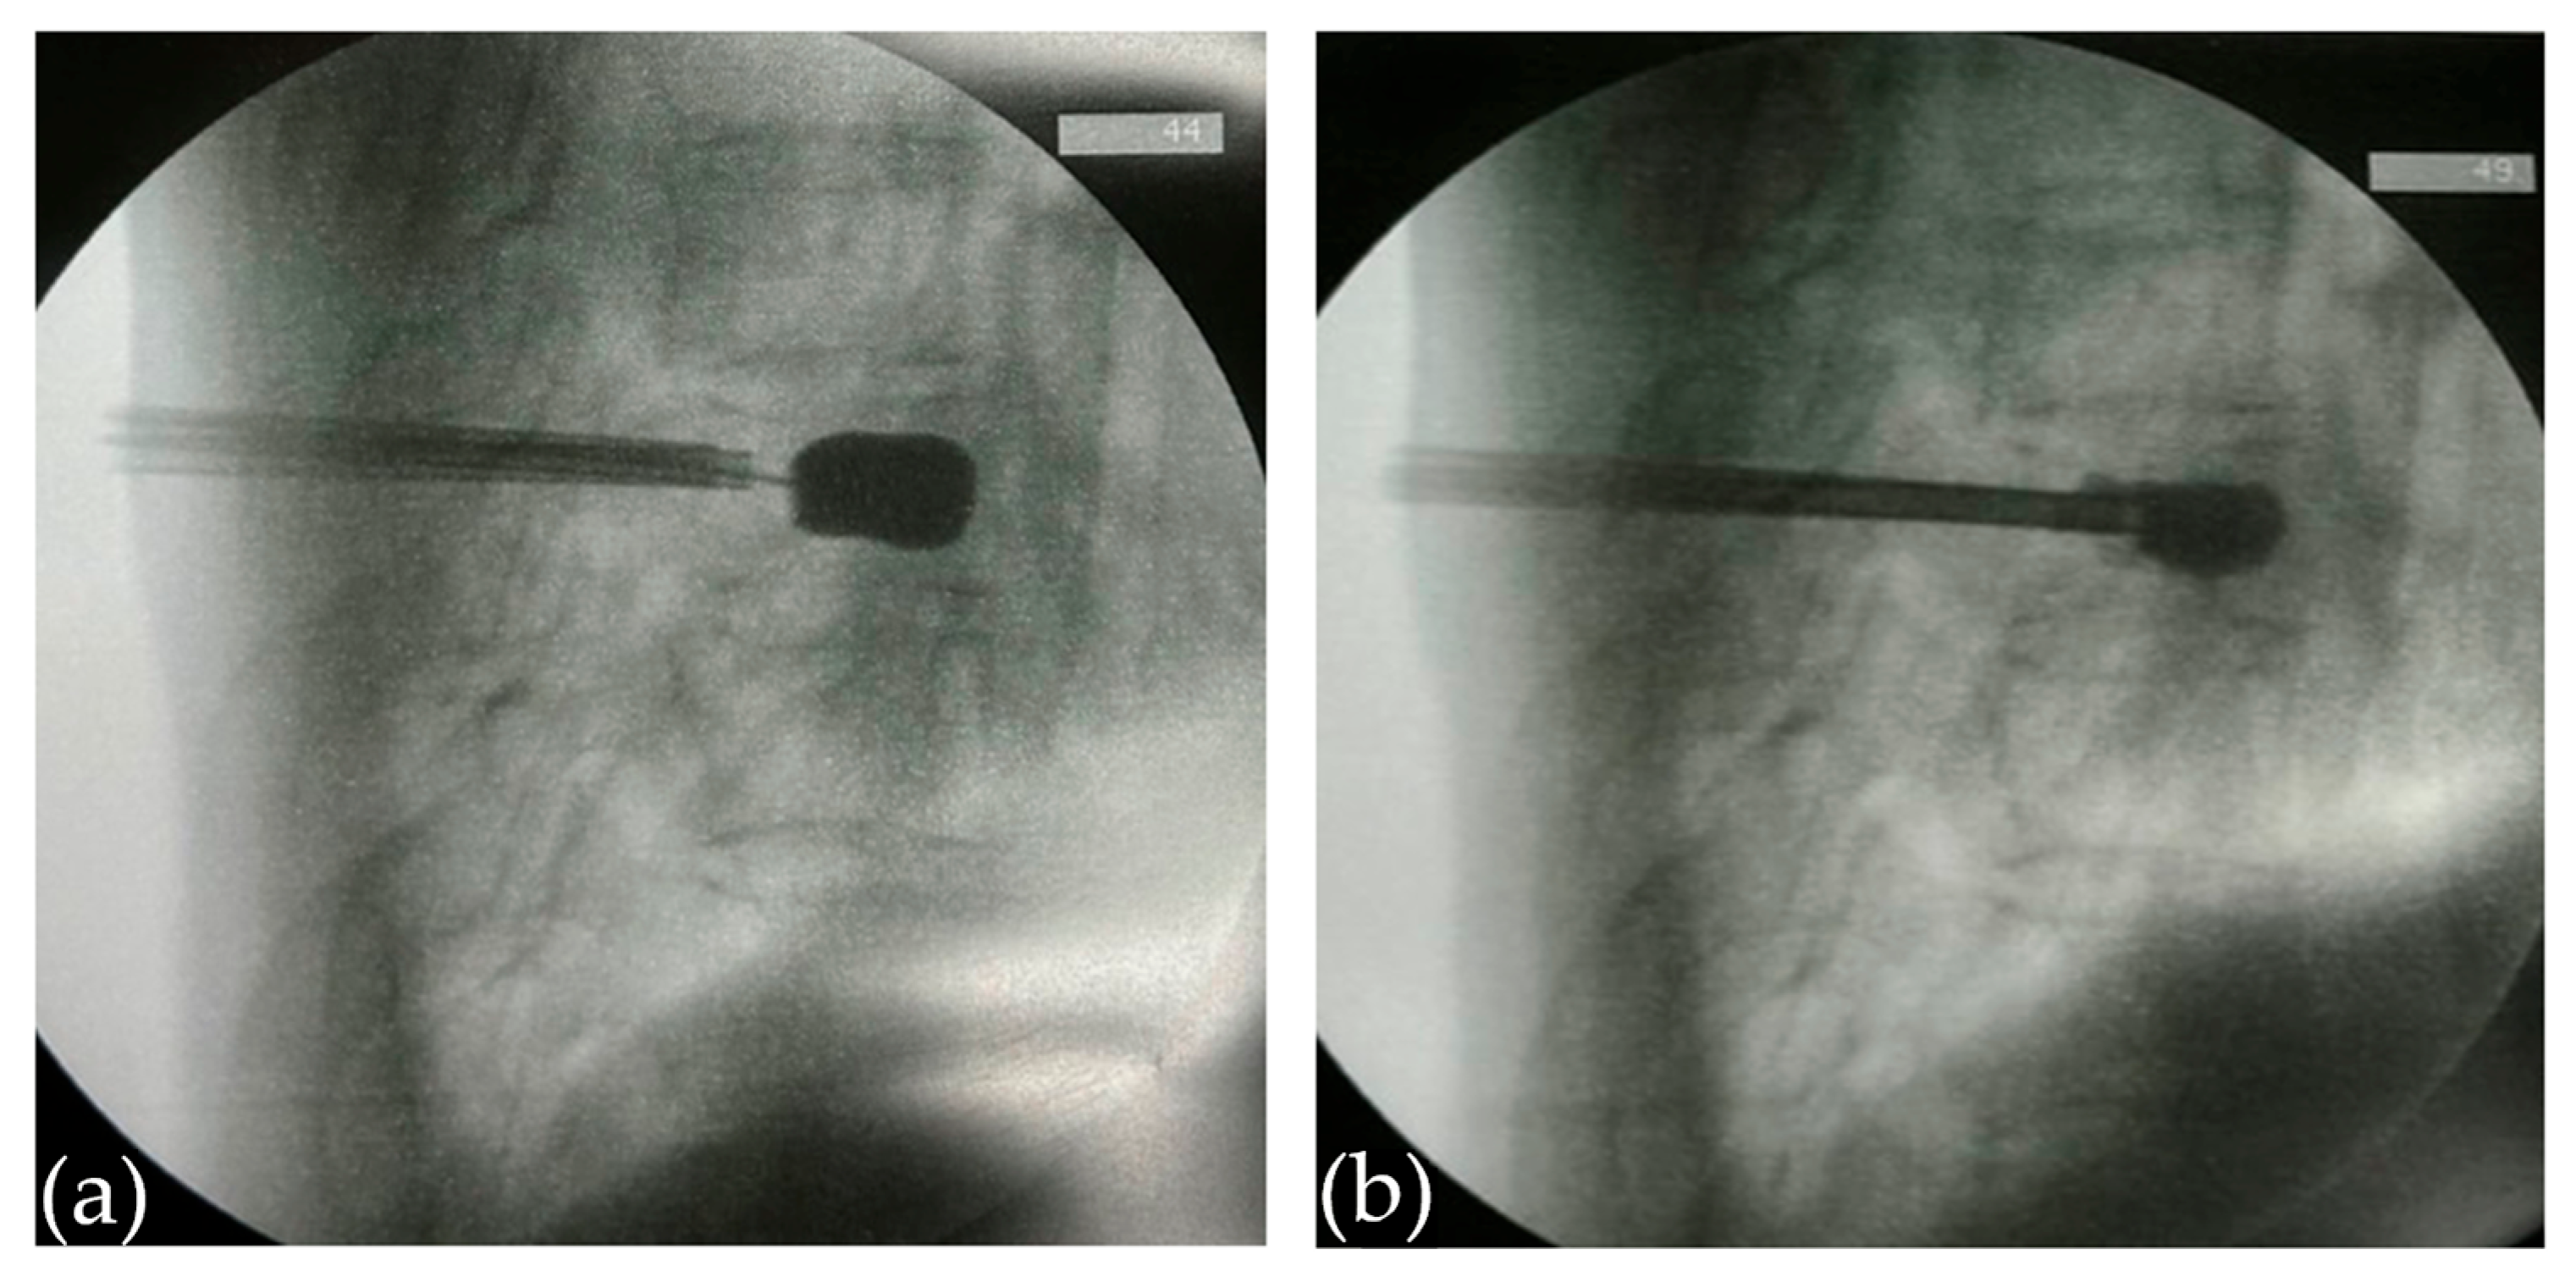

2.2.1. Creation of a Vertebral Cavity

2.2.2. Cement Preparation and Initial Injection

3.2. Decompression Maneuver